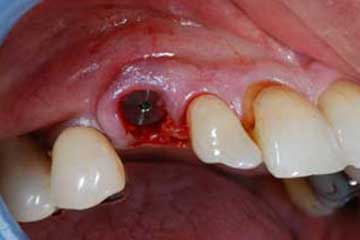

sono stati sostituiti da 10 impianti, cioè protesi radicolari endo-ossee che sostengono le protesi fisse superiore ed inferiore.